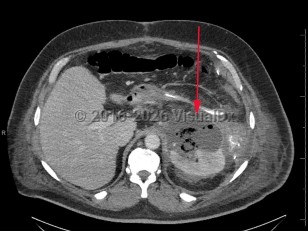

Perinephric abscess

A perinephric abscess is a collection of suppurative material in the perinephric space between the renal capsule and Gerota fascia. This condition is an uncommon complication of urinary tract infections, with incidence ranging from 1 to 10 cases for every 10 000 hospital admissions. Risk factors include diabetes mellitus (type 1, type 2) and renal stones.